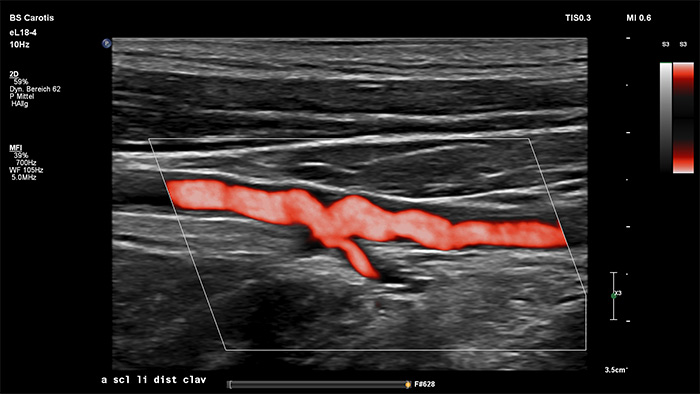

Philips MicroFlow Imaging è concepito per rilevare con considerevole sensibilità il flusso di sangue lento e debole nei tessuti e migliorare la risoluzione del flusso in esami vascolari. Grazie alla risoluzione elevata e agli artefatti ridotti al minimo, i medici sono in grado di visualizzare e caratterizzare piccole alterazioni del flusso attorno alla placca stenotica per formulare diagnosi affidabili.